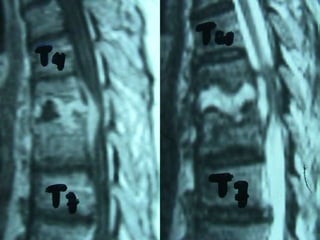

2nd case

Ma. Pal.

F 56 – Lawyer

MRI

Anterior procedure

Vertebrectomy - PUS evacuation + Stabilization

Posterior stabilization

2nd Post op.